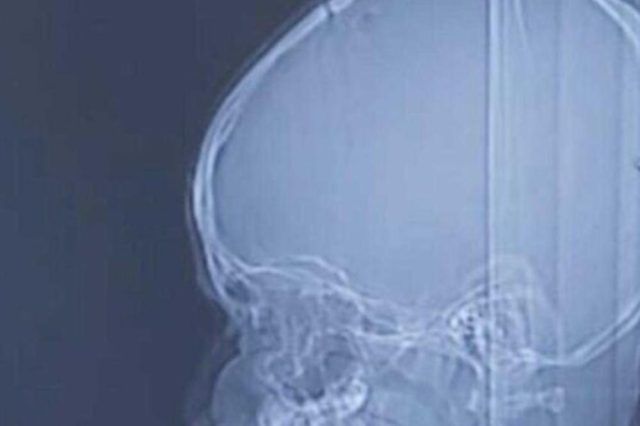

Nakon skeniranja, liječnici su pronašli uvrnutog parazita u pacijentovom mozgu. Chenu je dijagnosticirana sparganosis mansoni, rijetka parazitska bolest. Iako još uvijek utvrđuju točan uzrok njegovog stanja, liječnici kažu da je njegova infekcija posljedica nepijenja zaražene vode ili jedenja nedovoljno kuhanog mesa divljih životinja.

Chen se sada polako i uspješno oporavlja nakon što su mu liječnici iz mozga izvadili crva dugog nešto manje od 13 centimetara, a za kojeg se procjenjuje da je bio parazit oko 17 godina. Klikom na link OVDJE možete vidjeti fotografije crva.